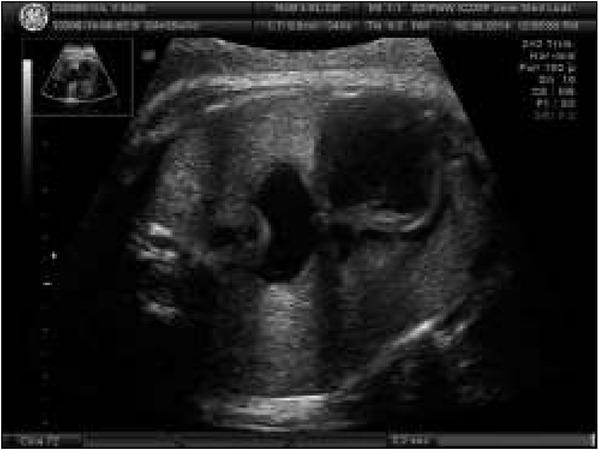

Fig. 2

Abnormal 4 chamber view of the fetal heart. Disproportion at the level of the atria and ventricles.Ryc. 2. Nieprawidłowy obraz 4 jam serca. Dysproporcja na poziomie przedsionków i komór.